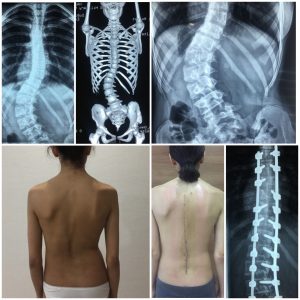

İDİOPATİK SKOLİOZ